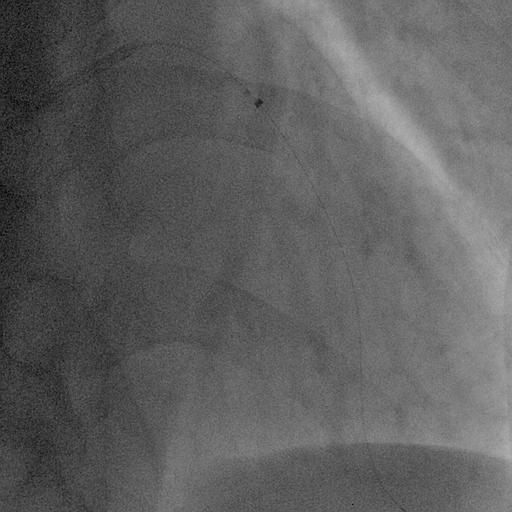

The target mid-LAD lesion was initially treated with excimer laser coronary angioplasty (ELCA) to ablate thrombotic tissue and facilitate subsequent vessel preparation. Following laser irradiation, prolonged low-pressure balloon dilatation was performed to optimize lesion modification and achieve adequate luminal expansion. Subsequently, a paclitaxel-coated drug-coated balloon (DCB) was applied at the treated segment to deliver antiproliferative therapy without stent implantation. Final angiography showed satisfactory luminal gain with TIMI 3 flow, and no evidence of vessel recoil or major dissection. Post-procedural OFDI confirmed a well-expanded lumen with smooth vessel surface, and no significant residual thrombus or flow-limiting dissection. The patient was discharged on dual antiplatelet therapy for 3 months. At 2-year follow-up, CCTA demonstrated sustained vessel patency without restenosis, supporting the long-term durability of this stentless ELCA+DCB strategy.